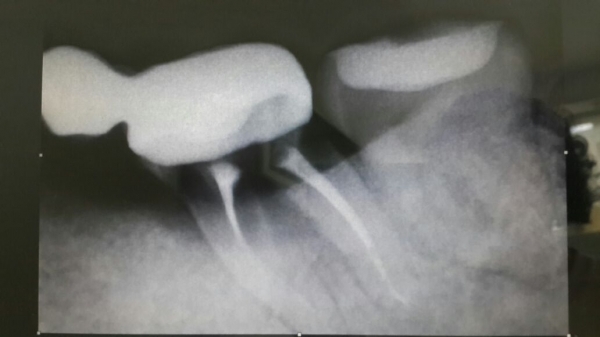

Дело в том, что я обычная пациентка. Несколько дней назад я пришла к своему доктору с болью. Мне сделали рентген и сказали, что зуб нужно удалять.

Зуб однозначно удаляется по причине открытой бифуркации.